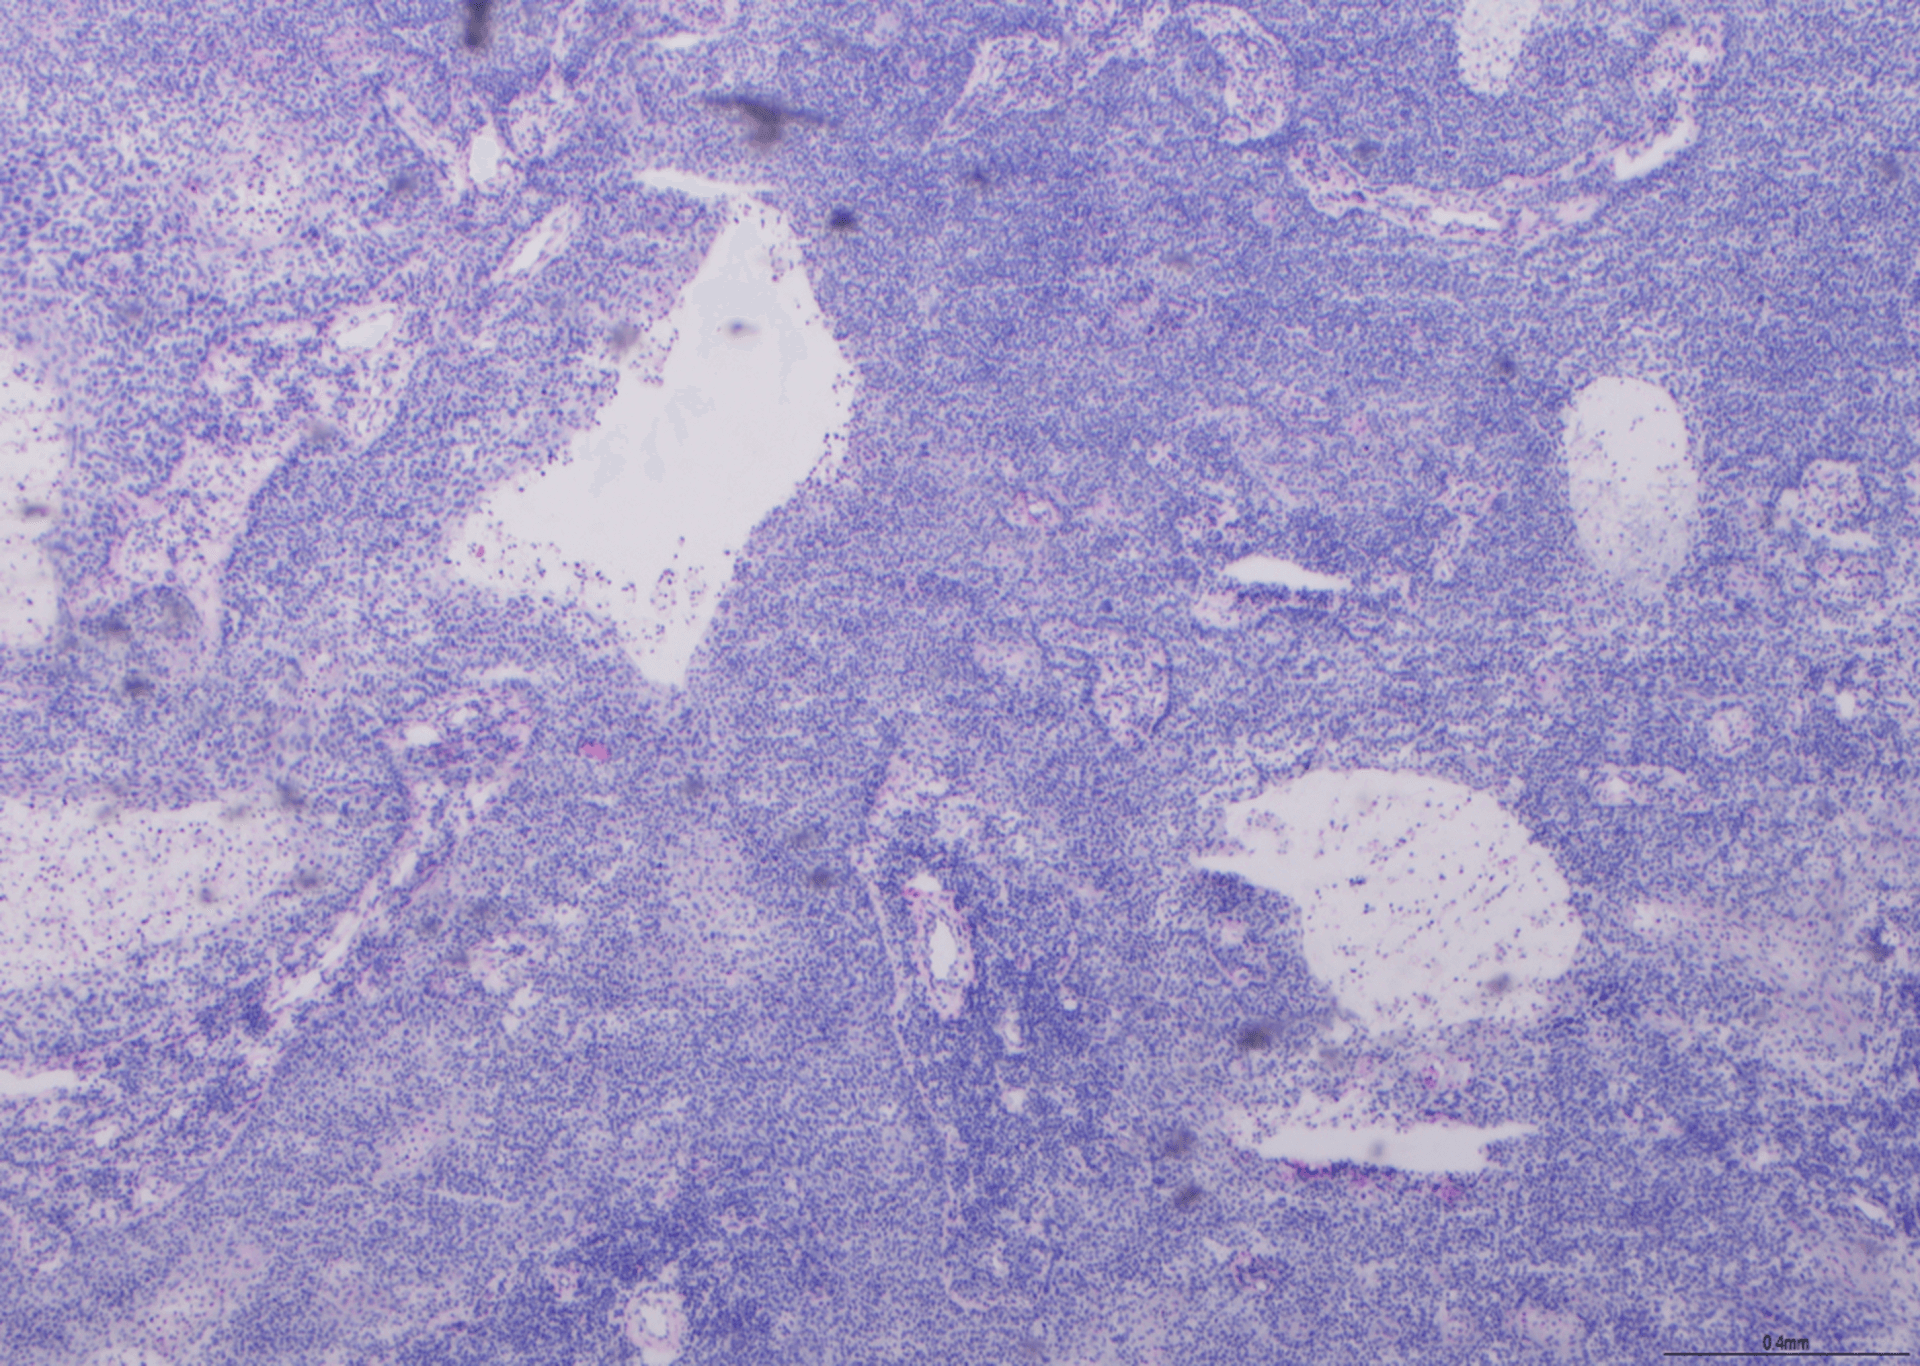

Reticulin Staining - BMT Scheme

This is an excellent example of retuculin staining. The silver has impregnated course and fine fibre networks with high specificity.

This scored 9/10.